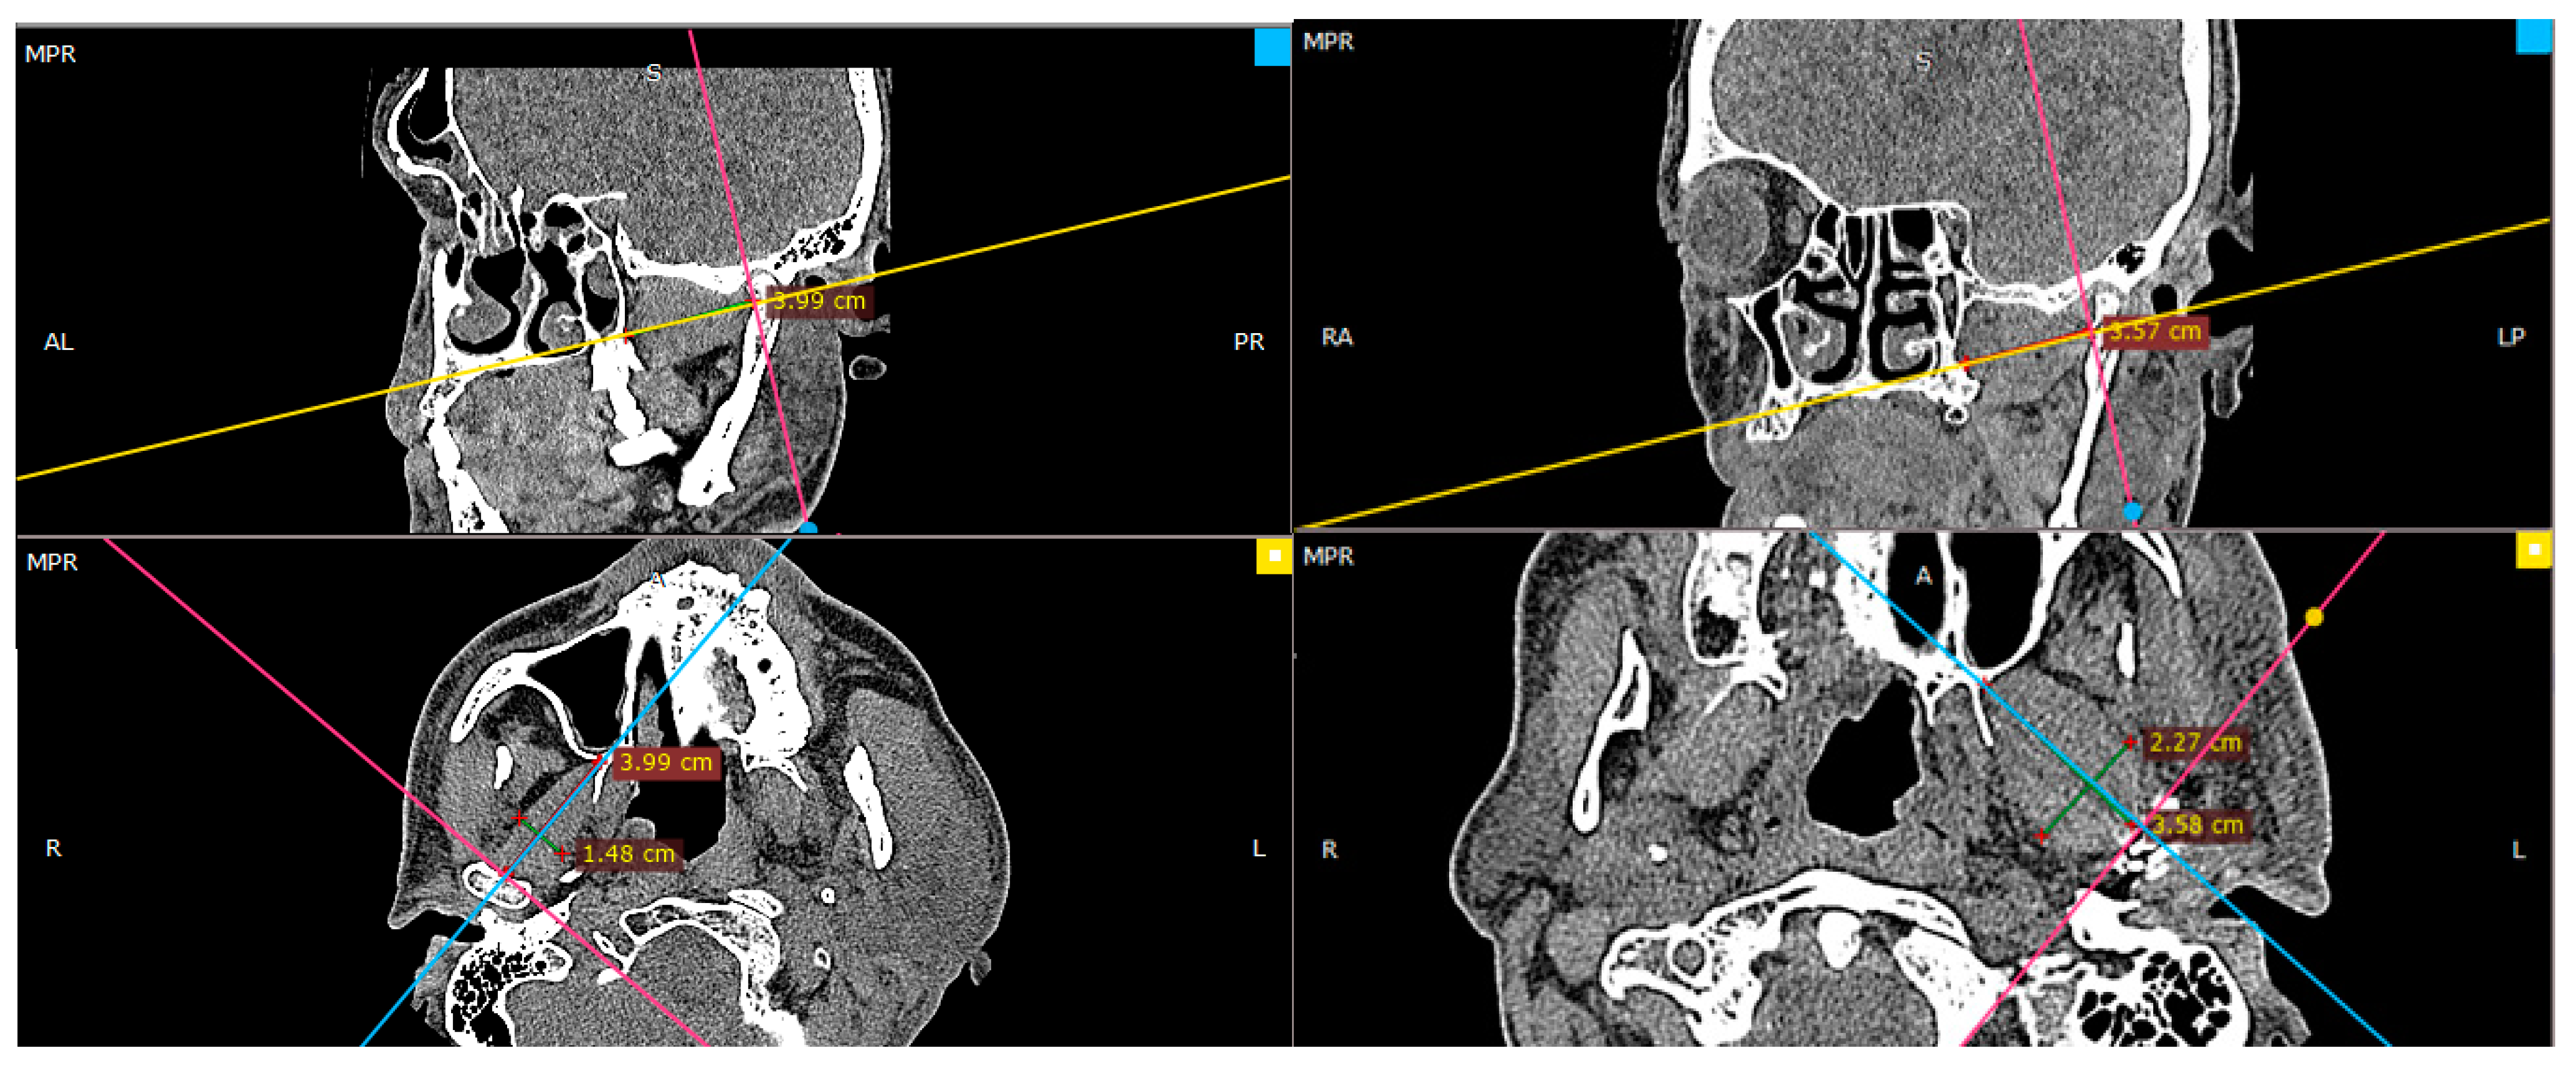

There is no doubt that surgical correction is the only way to restore the anatomical position of the mandibular head; however, the question is if it also improves the condition of the lateral pterygoid muscle, which, at first glance, right after the injury, shows significant asymmetry in terms of its shape (Figure 2).

Figure 2. Radiologic imaging study result in a patient with a fracture of the right mandibular head. Shortening of the right lateral pterygoid muscle (red arrow). Please note the length of the muscle on the intact side (blue arrow).